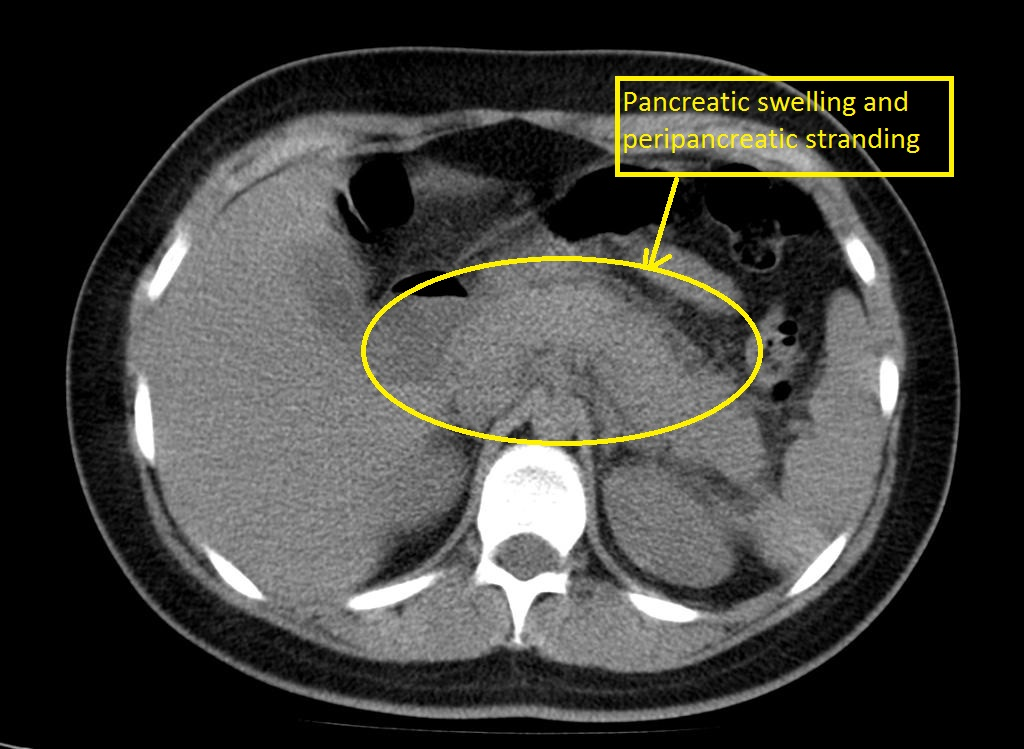

Acute Pancreatitis

• CT Abdomen